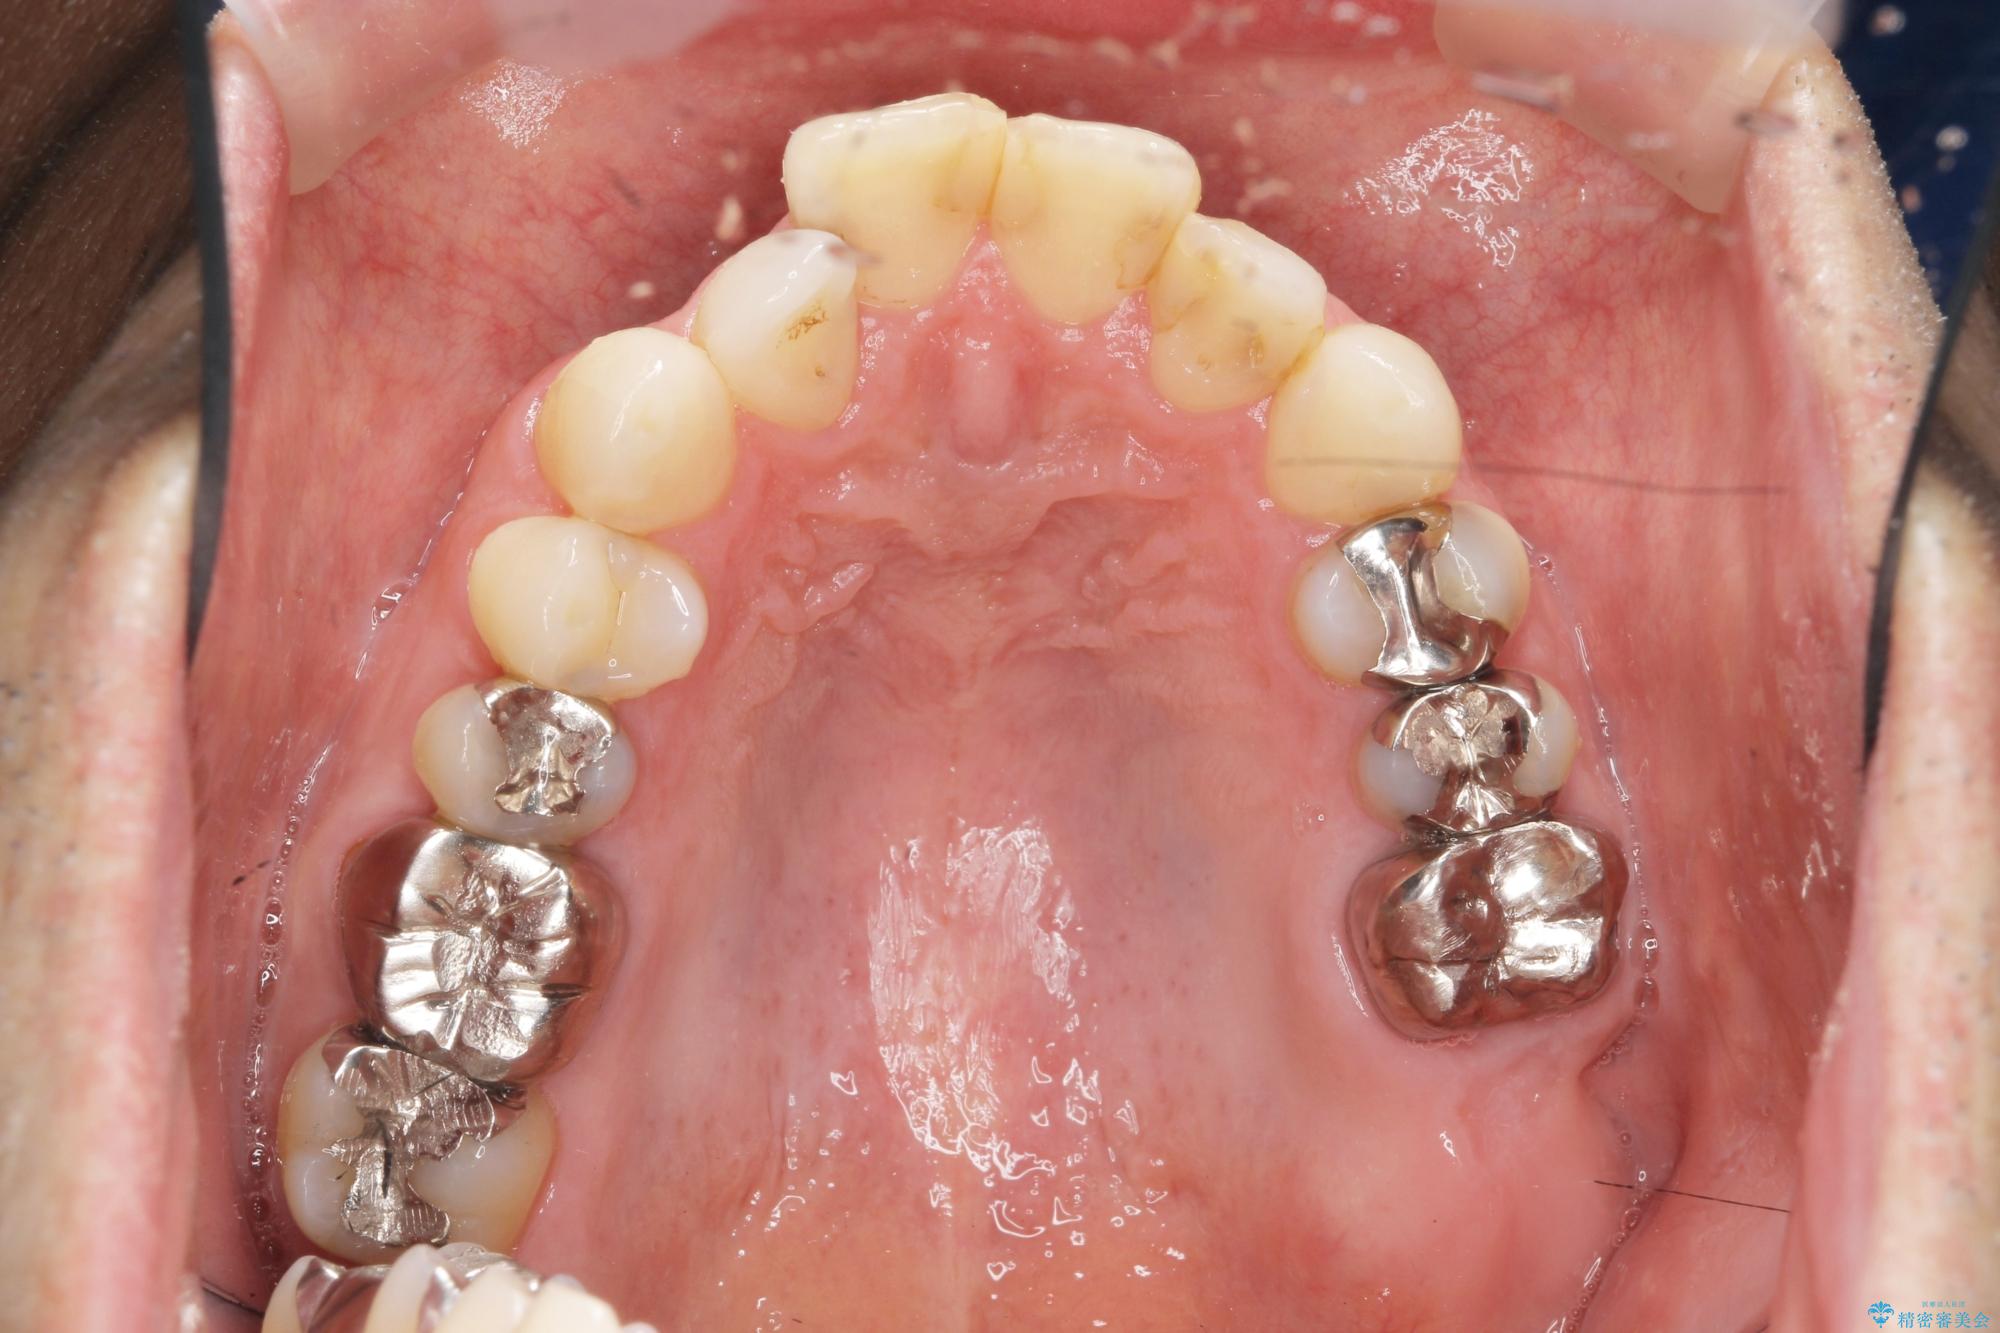

- 突き出た前歯の角度の改善と虫歯治療の改善を求めて来院されました。

虫歯を除去したのち、マウスピース矯正治療を行い、歯並びやがたつきを改善したのち、セラミックに置き換えることで審美性の向上を計画します。